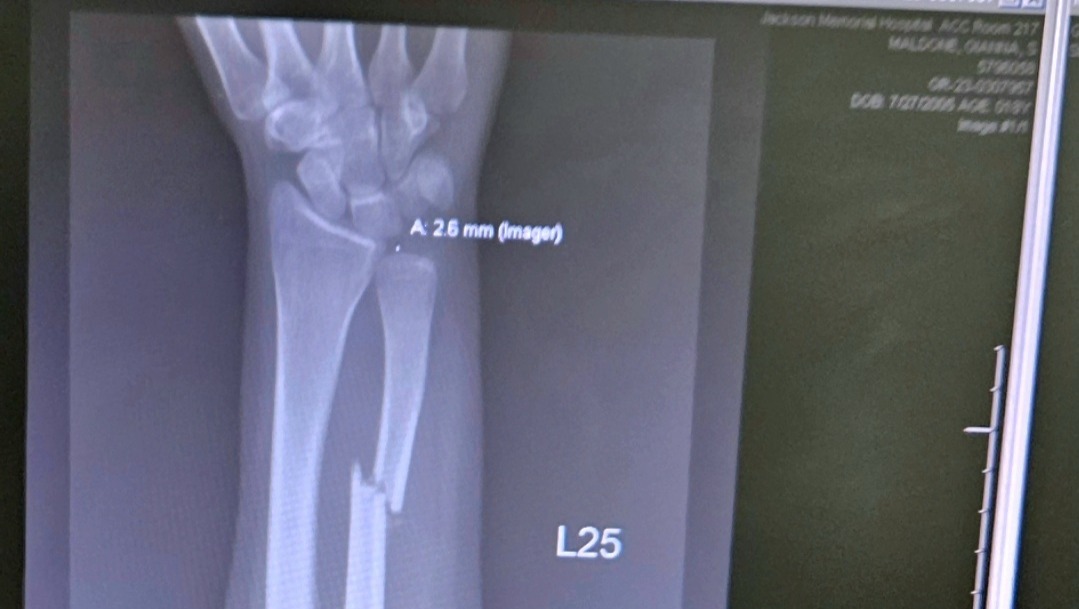

She received a broken cheek, broken orbital, broken nose, broken teeth, broken arm, broken jaw, brain hemorrhage, 2nd degree burns on her chest, arms and hands and was taken to Ryder Trauma center where she remained for almost one week in the burn unit, and receiving multiple CT scans daily.